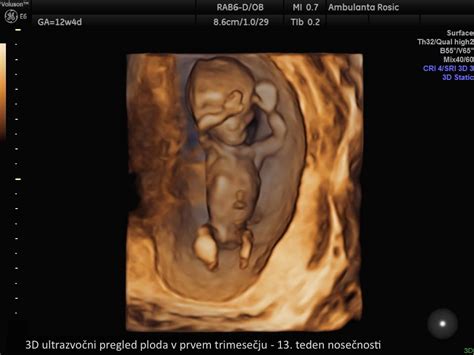

Sodobna medicina ponuja vrsto presejalnih testov, ki lahko že med nosečnostjo nakazujejo ali potrdijo prisotnost Downovega sindroma. Eden ključnih zgodnjih presejalnih pregledov je ultrazvočni pregled v 11. do 14. tednu nosečnosti, ki vključuje merjenje nuhalne svetline. Nuhalna svetlina je nakopičena tekočina v podkožju v predelu otrokovega vratu. Pri plodovih s kromosomskimi napakami, vključno s trisomijo 21, je ta tekočina običajno povečana. Poleg nuhalne svetline ultrazvočni pregled v tem obdobju omogoča tudi oceno prisotnosti nosne kosti, saj je njena odsotnost lahko znak povečanega tveganja za Downov sindrom.

Pomembno je poudariti, da je merjenje nuhalne svetline, skupaj z nekaterimi drugimi ultrazvočnimi meritvami, kot so merjenje glavice, srca in okončin, predvsem presejalni test. To pomeni, da rezultat izraža verjetnost ali tveganje za kromosomske nepravilnosti, ne pa dokončno diagnozo. Rezultati se pogosto izrazijo kot statistična verjetnost, na primer 1:300, kjer višje število pomeni manjše tveganje.